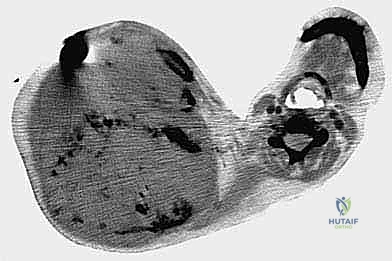

- التصوير الطبي المتقدم: استخدام الرنين المغناطيسي (MRI) لتقييم الأنسجة الرخوة، والأشعة المقطعية (CT scan) للصدر للبحث عن أي نقائل سرطانية (Metastasis)، والتصوير المقطعي بالإصدار البوزيتروني (PET Scan).

الخطوة 5: تحرير لوح الكتف والطرف (Scapular Mobilization)

ينتقل الجراح إلى الجزء الخلفي. يتم قطع العضلات التي تربط لوح الكتف بالقفص الصدري والعمود الفقري (مثل العضلة شبه المنحرفة، والعضلة الظهرية العريضة، والعضلات المعينية).

الخطوة 6: استئصال الورم والطرف (En Bloc Resection)

بمجرد تحرير جميع التوصيلات العظمية والعضلية والوعائية، يتم إزالة الطرف العلوي بأكمله مع الكتف والورم ككتلة واحدة، دون اختراق كبسولة الورم لضمان عدم تسرب الخلايا السرطانية.